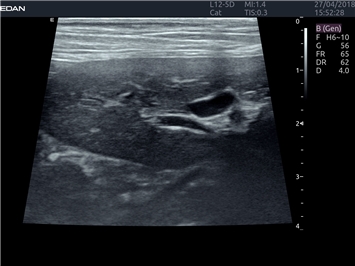

EDAN Acclarix LX4 VET представляет собой профессиональную ультразвуковую систему, специально разработанную для ветеринарных исследований. Сочетание стабильности, высокой производительности и эффективности делает эту систему идеальным выбором для современной ветеринарной практики.

Передовые технологии визуализации:

Инновационные технологии обработки изображений:

• Адаптивная визуализация тканей:

• Оптимизация изображения для различных видов животных

• Улучшенная детализация структур

• Универсальные датчики для различных видов животных

• Специализированные предустановки для ветеринарных исследований